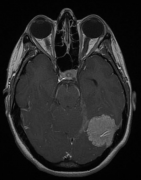

• 脑膜瘤的典型CT表现是什么?脑膜瘤MRI表现有哪些?

脑膜瘤的典型CT表现是什么?脑膜瘤MRI表现有哪些?

2021-08-04 10:48:50

脑膜瘤生长缓慢,常压迫周围组织引起相应的神经症状和体征,造成不同的障碍与肿瘤部位有关。脑膜瘤的典型CT表现是什么?脑膜瘤MRI表现有哪些?...